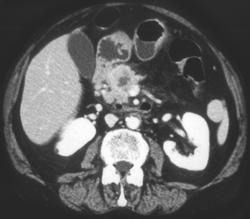

Fistulae From Duodenum to Pancreas